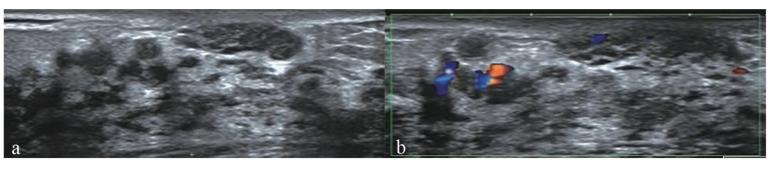

Objective: To develop a prediction model for discriminating malignant from benign breast non-mass-like lesions (NMLs) using conventional ultrasound (US), strain elastography (SE) of US elastography and contrast-enhanced ultrasound (CEUS). Methods: A total of 101 NMLs from 100 patients detected by conventional US were enrolled in this retrospective study. The characteristics of NMLs in conventional US, SE and CEUS were compared between malignant and benign NMLs. Histopathological results were used as the reference standard. Binary logistic regression analysis was performed to identify the independent risk factors. A multimodal method to evaluate NMLs based on logistic regression was developed. The diagnostic performance of conventional US, US + SE, US + CEUS and the combination of these modalities was evaluated and compared. Results: Among the 101 lesions, 50 (49.5%) were benign and 51 (50.5%) were malignant. Age ≥45 y, microcalcifications in the lesion, elasticity score >3, earlier enhancement time and hyper-enhancement were independent diagnostic indicators included to establish the multimodal prediction method. The area under the receiver operating characteristic curve (AUC) of US + SE + CEUS was significantly higher than that of US (p < 0.0001) and US + SE (p < 0.0001), but there was no significant difference between the AUC of US + SE + CEUS and the AUC of US + CEUS (p = 0.216). Conclusion: US + SE + CEUS and US + CEUS could significantly improve the diagnostic efficiency and accuracy of conventional US in the diagnosis of NMLs.